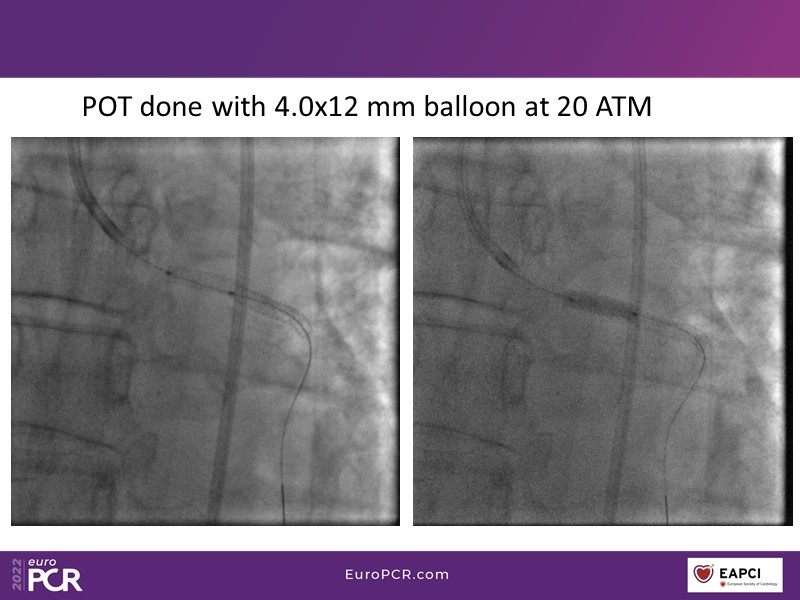

Alexandre Abizaid, Marco Valgimigli, Fazila Malik, Luca Testa, Patrick W. Serruys, Damiano Regazzoli, Kumar Prathap, and Sandeep Basavarajaiah take turns in this session to discuss two innovative technologies: a stent platform with nanotechnology and a novel drug-coated balloon (DCB). These novel technologies both have unique features that could change daily practice and improve outcomes.

- To find out more about the application and mechanism of a sirolimus coated balloon for coronary artery disease treatment with case presentations in complex settings

- To look at the technology behind the products, what the key data suggest and important takeaways from case permutations